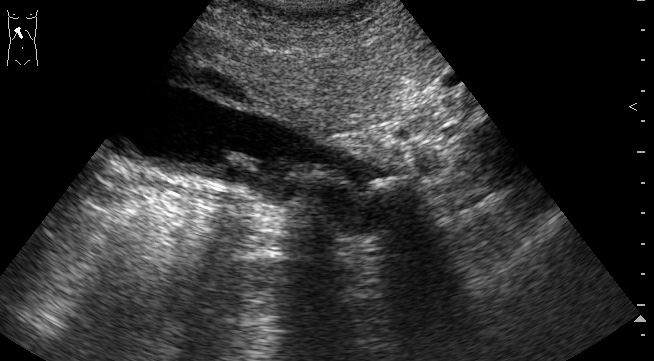

при поперечном сканировании на втором ролике, скопление свободной жидкости в паренхиме печени

Острый калькулезный гангренозный холецистит.

Особенность этого случая в том, что создается впечатление о перфорации стенки пузыря в области дна и наличии скопления желчи в области ложа пузыря.

В действительности перфорации стенки пузыря не было.